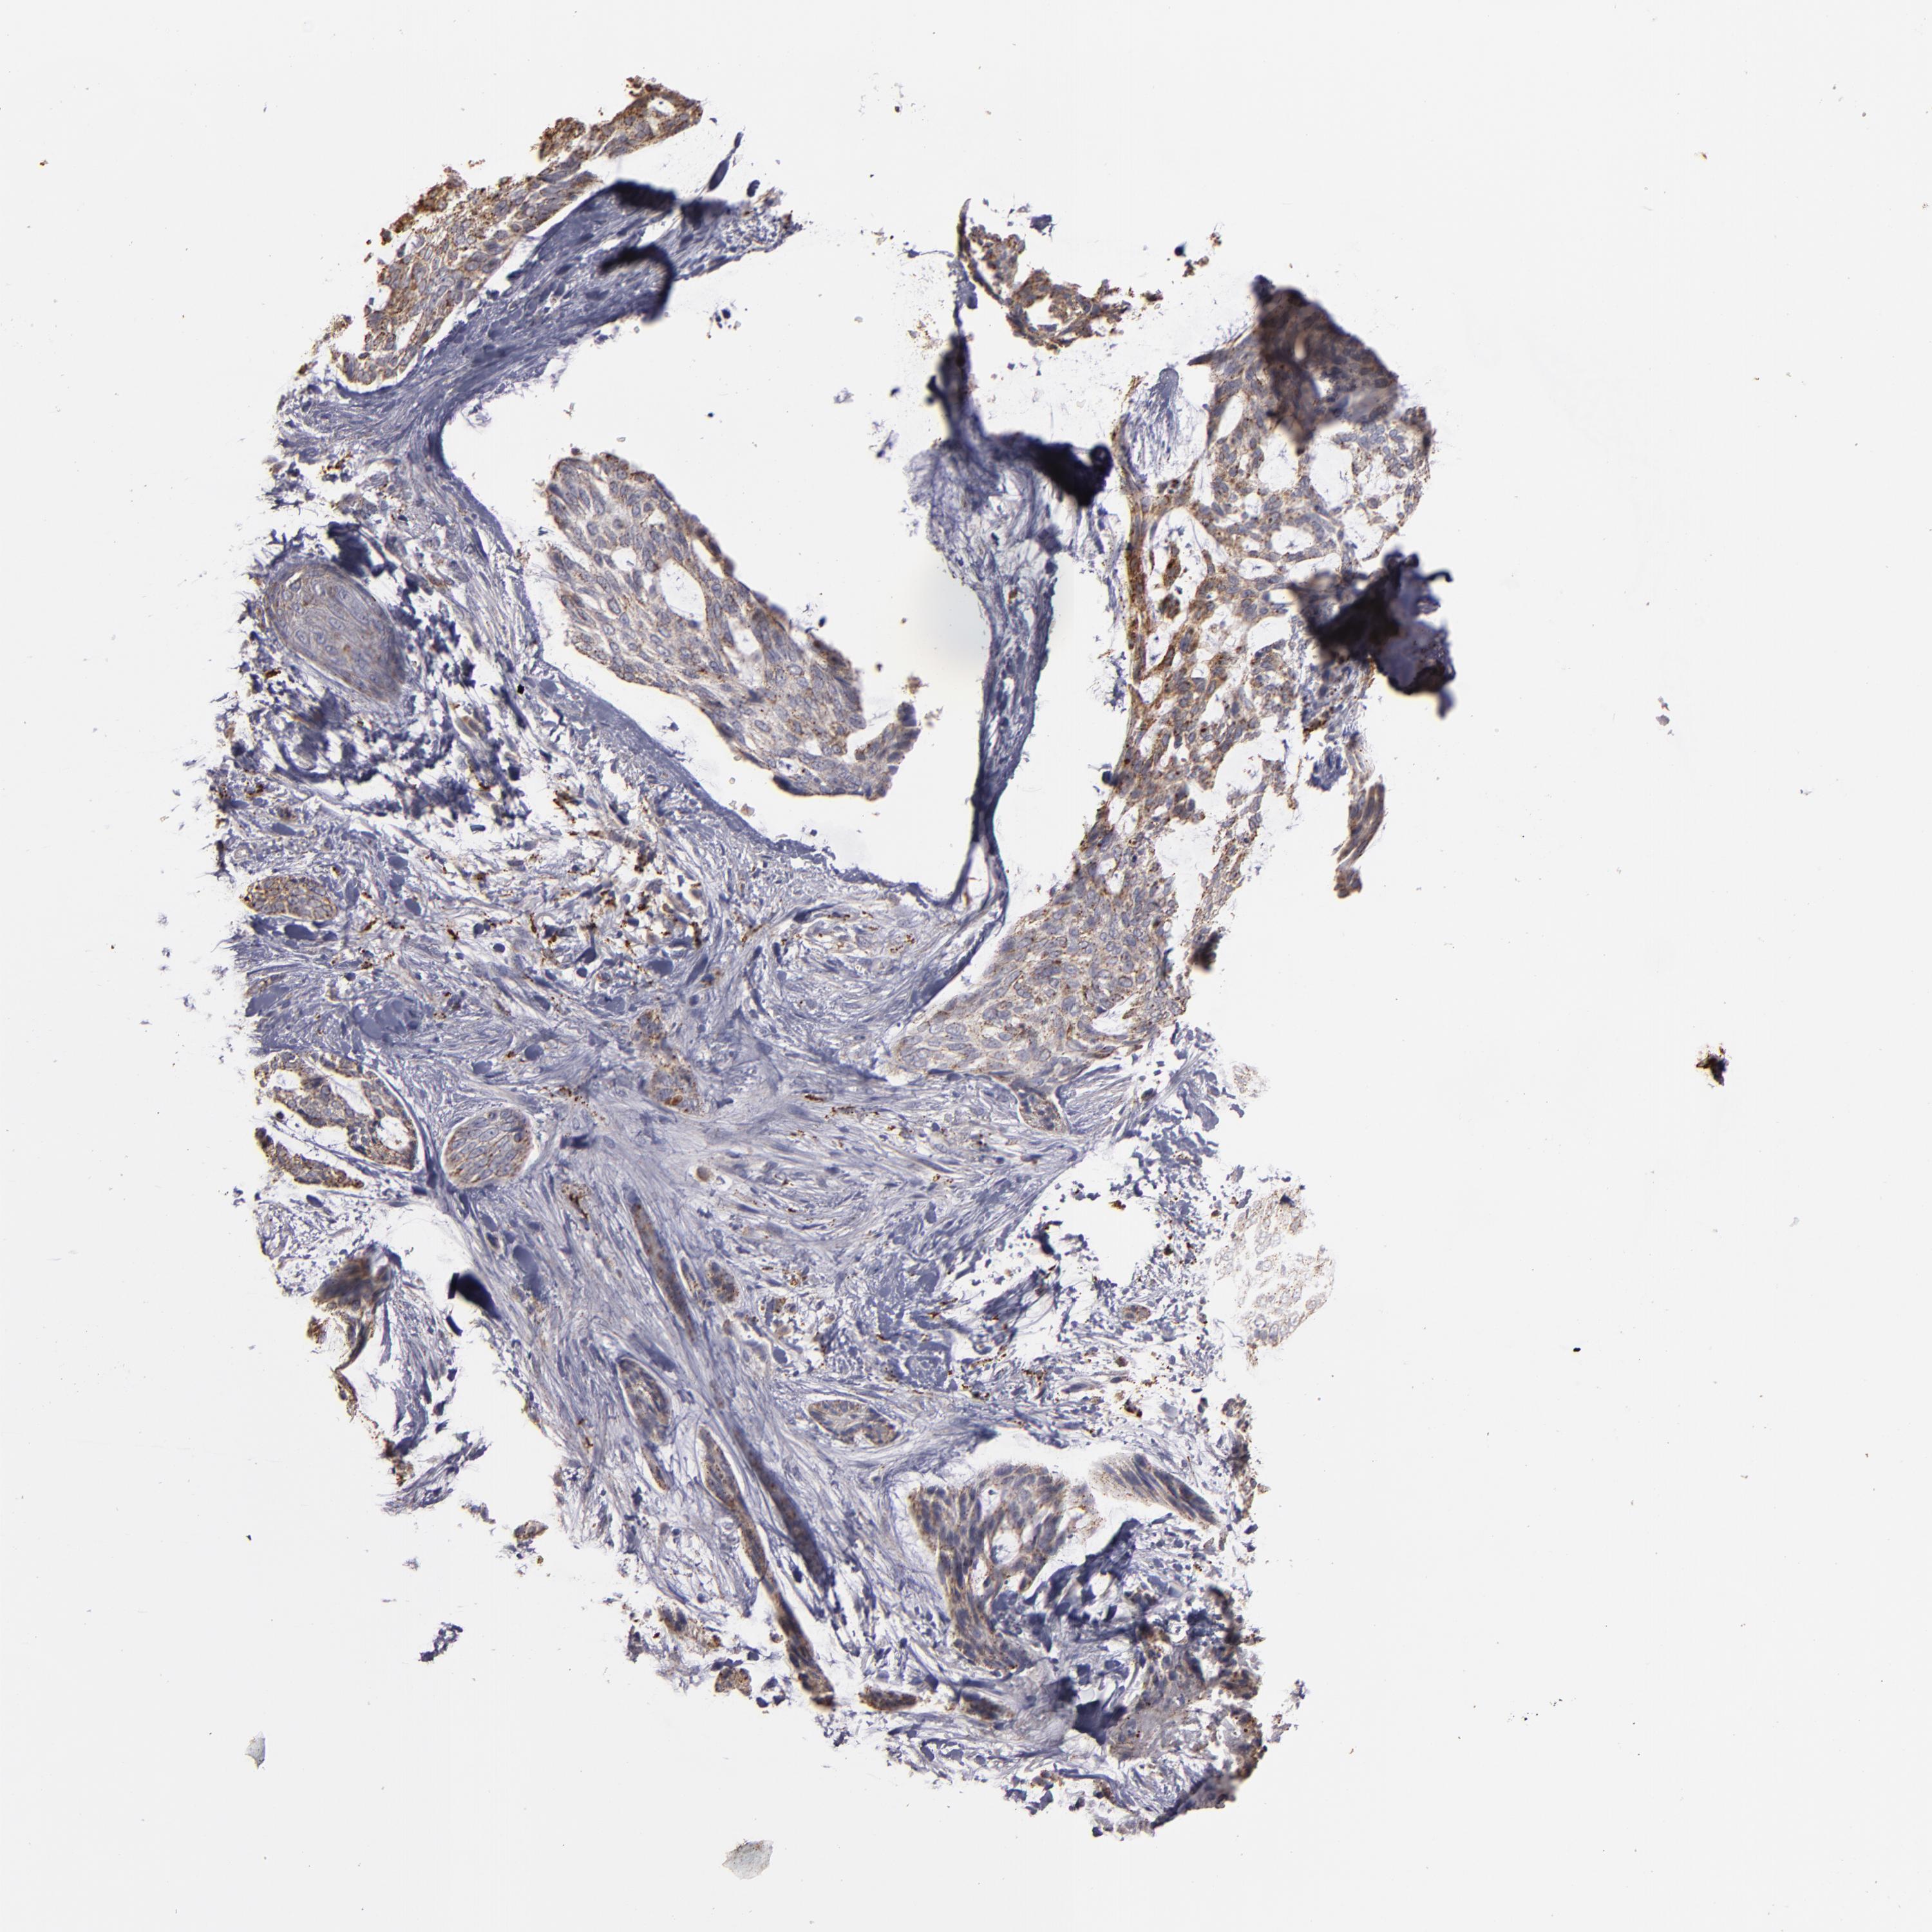

Basal cell and squamous cell cancer

SKIN CANCER - Protein expressioni

A mouse-over function shows sample information and annotation data. Click on an image to view it in a full screen mode. Samples can be filtered based on level of antibody staining by selecting one or several of the following categories: high, medium, low and not detected. The assay and annotation is described here.

Antibody stainingi

Antibody staining in the annotated cell types in the current human tissue is reported as not detected, low, medium, or high, based on conventional immunohistochemistry profiling in selected tissues. This score is based on the combination of the staining intensity and fraction of stained cells.

Each image is clickable and will lead to virtual microscopy that enables deeper exploration of all samples and also displays staining intensity scores, fraction scores and subcellular localization as well as patient and tissue information for each sample.

Antibody CAB009593

Staining

High

Medium

Low

Not detected

Intensity

Strong

Moderate

Weak

Negative

Quantity

>75%

75%-25%

<25%

None

Location

Nuclear

Cytoplasmic/membranous

Cytoplasmic/membranous,nuclear

Squamous cell carcinoma, NOS

Basal cell carcinoma